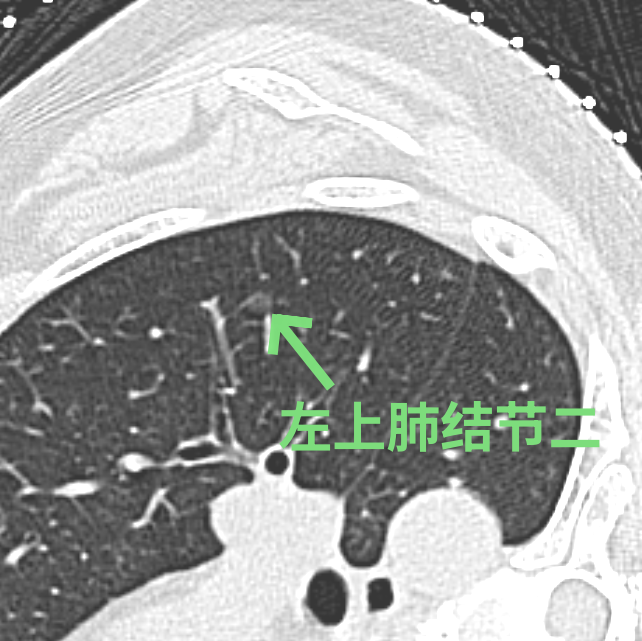

刘女士在体检时发现左肺有3个高危的磨玻璃结节,慕名找到我院胸部医学中心徐驯宇主任医师团队。在分析了刘女士的肺部影像资料后,徐驯宇发现刘女士左上肺的两个结节位置较浅表,其中一个结节最大径仅4.5mm,这类大小的结节在手术中不易定位;而左下肺的结节位置较深,如果全部采用手术切除的方法,将损失较多的正常肺组织,得不偿失。

经过徐驯宇主任医师、黄郴副主任医师和王捷阳医师的反复讨论,决定为刘女士实施杂交手术:首先由黄郴和王捷阳在CT引导下为刘女士左上肺的小结节打上金属钩作为标记,然后再对左下肺较深的结节进行热消融治疗;接着由徐驯宇主刀为刘女士进行胸腔镜下左上肺结节的切除。在术中,徐驯宇按照之前在CT引导下置入的金属钩,很快就定位到左上肺的磨玻璃结节,并进行精准的局部切除,整个过程仅耗时30分钟。术后的病理报告显示,这3个结节分别为两个原位癌和一个非典型腺瘤样增生。经过量身定制的杂交手术,刘女士顺利解除了肺部的3个健康隐患,3天就顺利恢复出院。